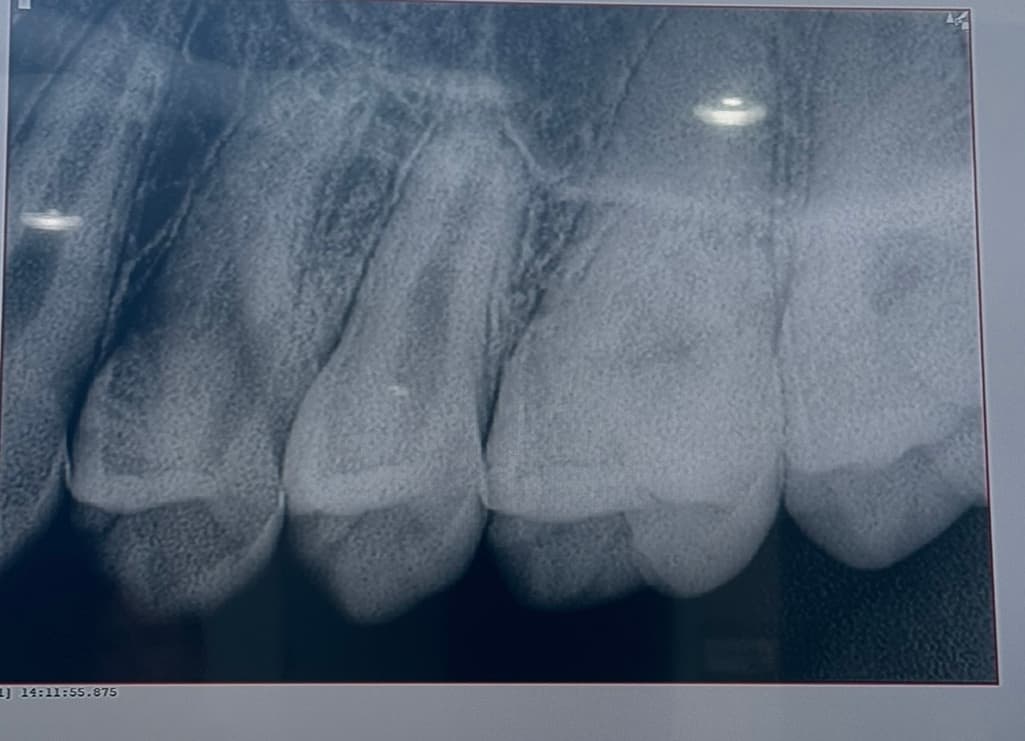

25~26 치아고 첫번째, 세번째 사진이 최근 두번째 사진이 올해 2월 입니다 인접면 충치가 맞는지 얼마나 진행되었는지 궁금합니다

엑스레이 상에서 명확히 관찰되지는 않는 것으로 보이며 관리 하면서 지켜봐도 될 것 같습니다.

엑스레이 상으로는 인접면 충치가 심해 보이진 않으니 일단은 관리를 해서 사용해보셔도 될것같습니다.

25~26 치아고 첫번째, 세번째 사진이 최근 두번째 사진이 올해 2월 입니다 인접면 충치가 맞는지 얼마나 진행되었는지 궁금합니다 -> 25,26 사이 인접면 충치 크게 문제 없어 보입니다